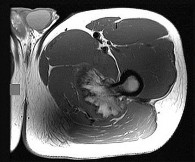

Question 8

A 28-year-old male sustained a displaced talar neck fracture and underwent open reduction and internal fixation.

Six weeks postoperatively, a subchondral radiolucent band is seen in the talar dome on the AP mortise radiograph. What does this radiographic finding indicate?

Explanation

Hawkins sign is a subchondral radiolucent band seen in the talar dome 6 to 8 weeks after a talus fracture. It represents subchondral osteopenia secondary to disuse atrophy. Because bone resorption requires an active blood supply, the presence of a Hawkins sign is a highly reliable indicator that the talar body has intact vascularity and that avascular necrosis (AVN) is unlikely.